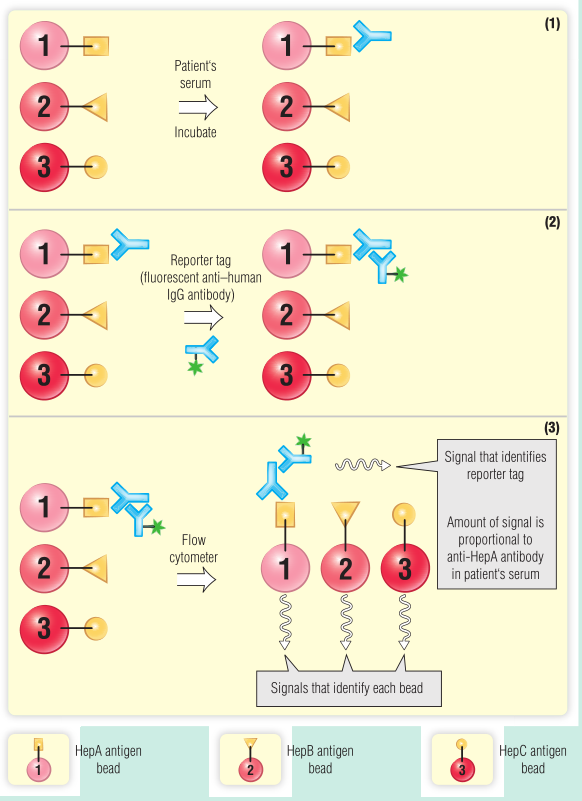

BOX 5.3 临床诊断实验室新技术–荧光微球免疫分析

一种被称为Luminex xMAP技术的新诊断测试方法,似乎非常有价值,特别是在小体积样本上进行多项测试时。这项技术利用了酶联免疫吸附试验(ELISA)和流式细胞术两个方面。本质上,聚苯乙烯微球内部用两种荧光染料进行颜色编码,这两种染料可以在激光照射后检测到。通过混合不同的染料,最多100颗珠子中的每一颗都可以被赋予一个独特的身份(“光谱信号”),这可以在流式细胞仪中检测到(参见Fig 5.7)。每颗珠子还可以涂上不同的化合物,如抗体、寡核苷酸和酶,这些化合物可以从测试样本中收集分子。通过使用带有不同颜色荧光报告标签的夹心法(如Fig 5.11所示),可以用第二个激光测量化合物(例如,肝炎病毒抗体)的量。微球溶解在微滴定孔或试管中,并且多个珠子可以存在于单个容器中。每一颗珠子都可以用不同的反应物衍生化,一组100颗珠子可以分析多达100种不同的化合物。珠子在液体中被输送到分析仪中,并受到激光照射,很像流式细胞仪中的单个细胞(见Fig 5.7)。这项技术可以用来在很短的时间内从少量的样品中进行多项测试,称为多重测试。结果表明,该检测方法灵敏、特异,与ELISA等其他检测方法相比具有一定的优势。

下面是可以使用该测试的一个示例。一个病人在出国旅行后不久就出现了黄疸。病人声称在旅行期间没有高危行为史,然后他被要求检测肝炎病毒抗体。采集血液样本,血清用于检测甲型、乙型和丙型肝炎病毒抗体的存在。如图所示,患者血清中含有与表达甲型肝炎抗原的Luminex小球结合的抗体,而不是与表达乙型肝炎或丙型肝炎抗原的小球结合的抗体。患者接受甲型肝炎治疗,黄疸消退。

微球微珠检测的一个优点是能够同时检测多种反应物,例如一组病毒抗原或一组细胞因子。

Fig 5.11 基于荧光微球的肝炎病毒抗体免疫分析(Luminex xMAP技术)